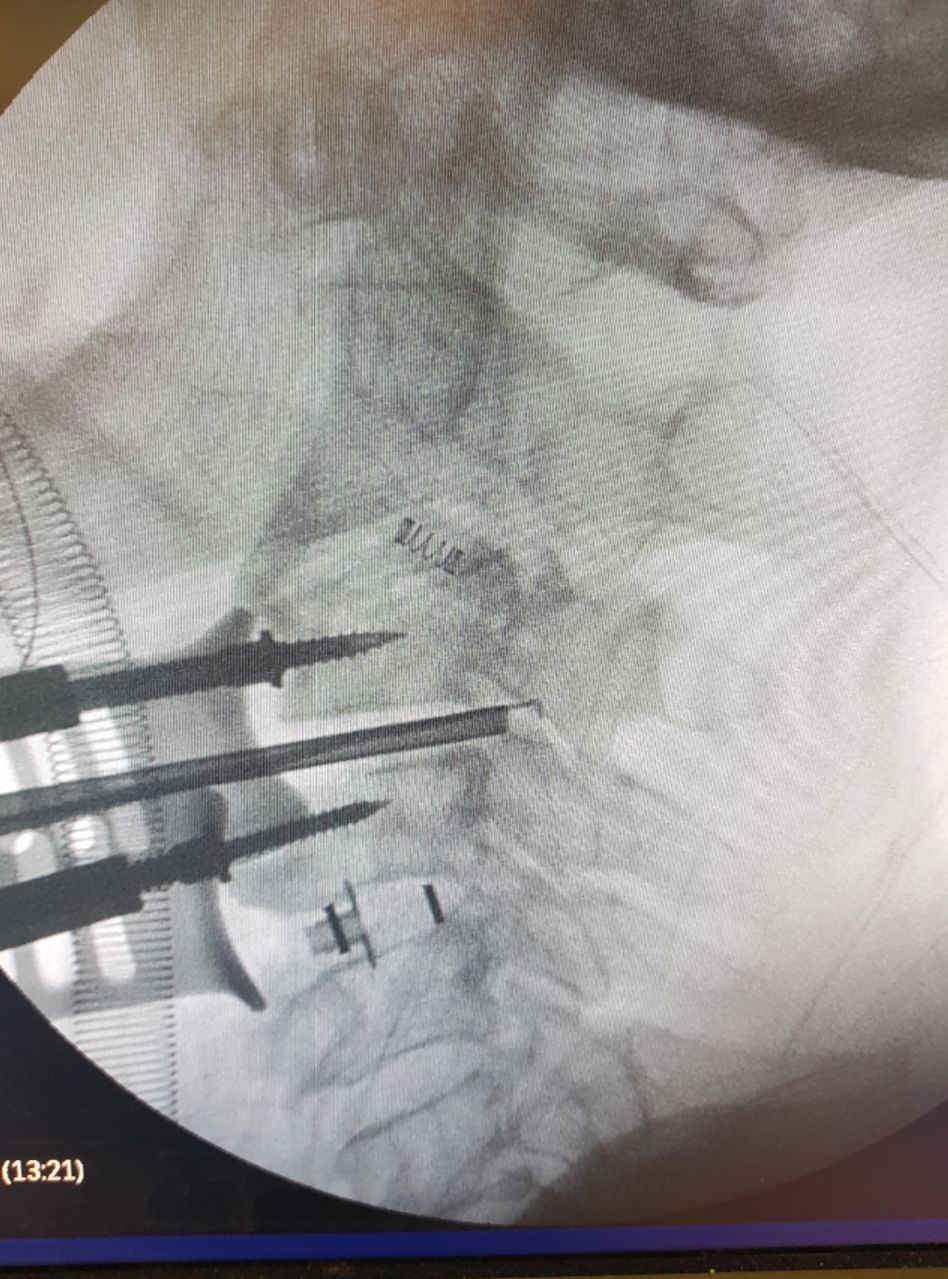

Διεγχειρητική απεικόνιση οπίσθιας σπονδυλοδεσίας ΑΜΣΣ με O ARM